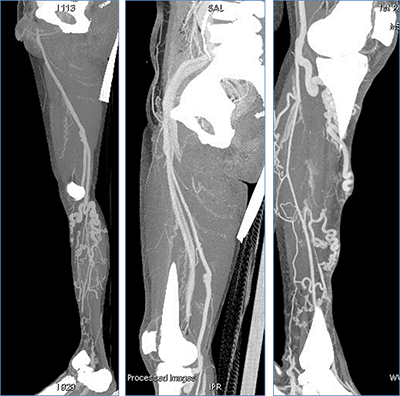

影像表现: 间接法CTV,双侧下肢深、浅静脉同时显影,深静脉通畅,广泛浅静脉曲张

能谱60kev单能量、VR成像 双侧下肢浅静脉 呈蚓状曲张改变

60kev 自动去骨VR成像,深静脉与浅静脉同时显影,浅静脉多发蚓状迂曲改变

50kev、MIP成像 深、浅静脉同时充盈, 未见充盈缺损(无栓子)。 提示深静脉通畅,浅静脉曲张可能由压力、瓣膜功能不良等其它因素产生。